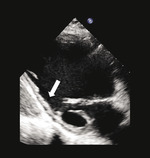

Rycina 1. Spoczynkowe przezklatkowe badanie echokardiograficzne (projekcja przymostkowa w osi krótkiej i zmodyfikowana projekcja koniuszkowa) u pacjenta po rozległym zawale ściany dolnej przebytym 5 lat wcześniej. Ściana dolna charakteryzuje się znacznym zmniejszeniem grubości końcoworozkurczowej (5 mm, strzałki), co wskazuje na obecność blizny i nieodwracalnego uszkodzenia